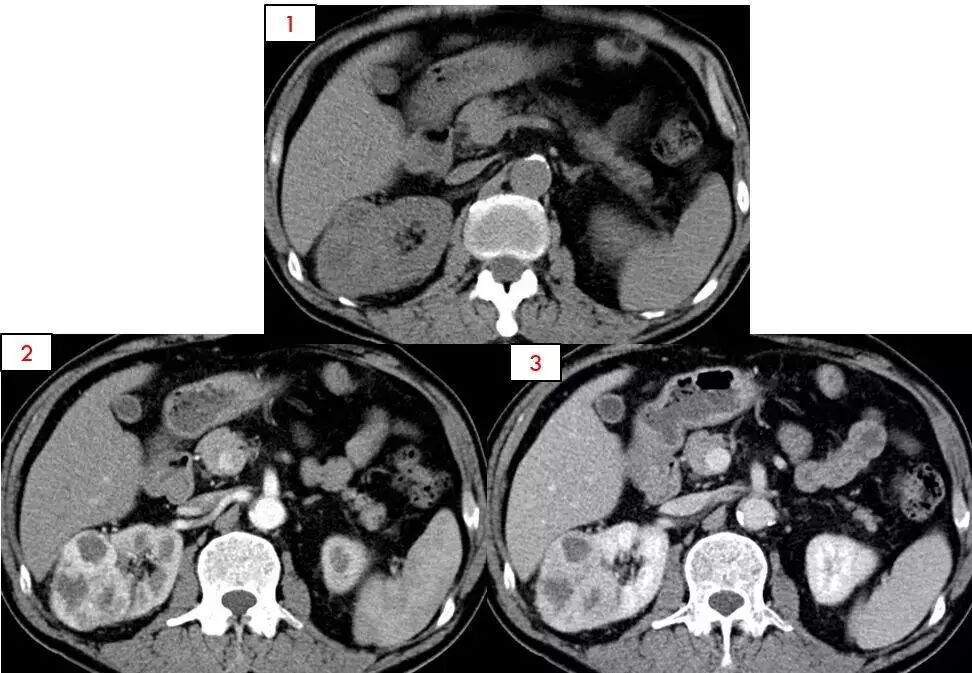

肾癌

高明觉察到了继父不对劲,于是将他送到了沈阳中医院进行详细检查,结果发现他身体的癌细胞已经扩散到肺部、腰部等地方,全身一共检查出9处肿瘤。